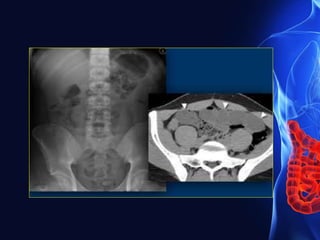

CT-Scan

• CT confirms obstruction with a colonic diameter

of >5.5 cm (9 cm in the caecum) considered

abnormal.

• Identification of a transition point indicates the

level of obstruction.

• CT clearly demonstrates intramural gas,

Colonic carcinoma

• Focal irregular bowel-wall thickening with proximal

dilatation.

• There may be inflammatory stranding in the

Axial and coronal images demonstrating large-bowel

obstruction (asterix) secondary to a colonic carcinoma

in the distal descending colon (arrow).